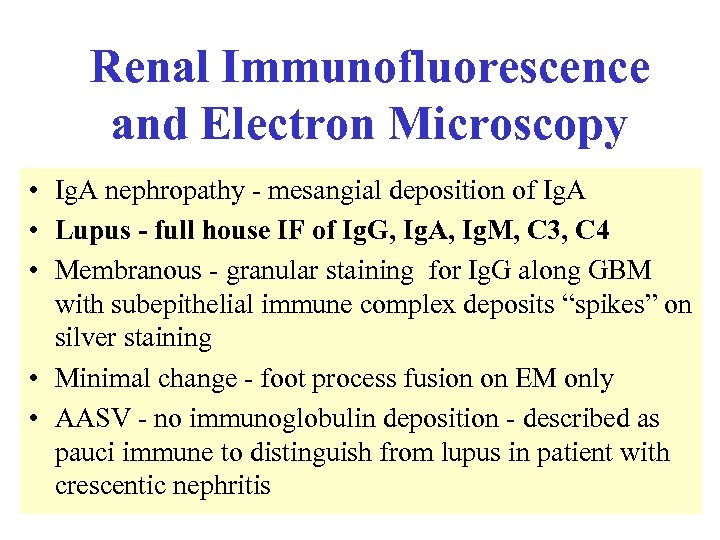

Renal Immunofluorescence and Electron Microscopy • Ig. A nephropathy - mesangial deposition of Ig. A • Lupus - full house IF of Ig. G, Ig. A, Ig. M, C 3, C 4 • Membranous - granular staining for Ig. G along GBM with subepithelial immune complex deposits “spikes” on silver staining • Minimal change - foot process fusion on EM only • AASV - no immunoglobulin deposition - described as pauci immune to distinguish from lupus in patient with crescentic nephritis

Renal Immunofluorescence and Electron Microscopy • Ig. A nephropathy - mesangial deposition of Ig. A • Lupus - full house IF of Ig. G, Ig. A, Ig. M, C 3, C 4 • Membranous - granular staining for Ig. G along GBM with subepithelial immune complex deposits “spikes” on silver staining • Minimal change - foot process fusion on EM only • AASV - no immunoglobulin deposition - described as pauci immune to distinguish from lupus in patient with crescentic nephritis